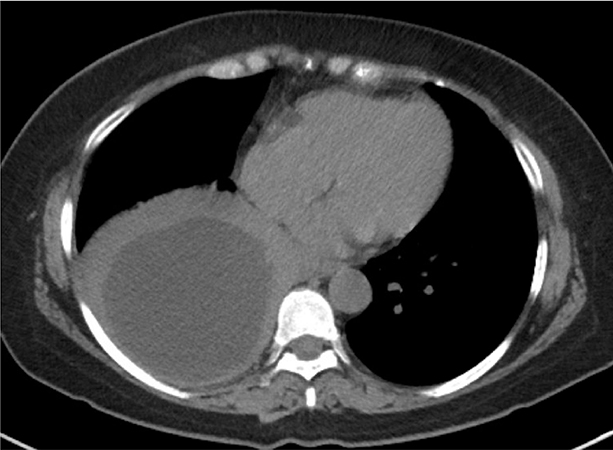

Clinical History: A 63-year-old woman, never-smoker, with a history of type 2 diabetes and hypothyroidism presented with one week of fevers, cough, and shortness of breath. Three months earlier she was living in Peru. CT scan of the chest showed a thick-walled cystic mass (10.8 cm) in the right lower lobe, favored to represent an abscess (Figure 1). She was empirically started on broad spectrum antibiotics and albendazole, and subsequently underwent a thoracotomy with right lower lobectomy. Grossly, the cyst was unilocular with an intact thick white fibrous capsule and filled with yellow gelatinous material. Microscopic examination showed the outer cyst wall contained dense fibrosis (Figure 2) with necrotizing granulomatous inflammation in the adjacent lung parenchyma (Figure 3). There was a laminated membrane composed of acellular material with a zebra-like pattern of lamellar lines (Figure 4). At higher magnification, the cyst contained several intracystic organisms (Figures 5 and 6). The patient was discharged home post-operatively with six months of albendazole therapy.

Diagnosis can often be made clinically using a combination of imaging and serology. Chest radiograph shows single or multiple oval masses with smooth borders surrounded by normal lung. CT scan of the chest shows single or multiple fluid-filled cysts which can be large in size. If the cyst is intact, it may show a thin enhancing rim with homogenous contents and occasionally multiple daughter cysts can be identified. Calcification of pulmonary cysts is uncommon. Serum antibodies for echinococcal antigens are detectable in about half of patients with pulmonary cysts. Percutaneous aspiration is considered too risky for diagnosis due to the possibility of cyst rupture and anaphylaxis, although inadvertent aspiration may yield protoscolices and hooklets. Surgical resection is the treatment of choice for pulmonary echinococcal cysts with complete removal of the intact cyst. Medical therapy (e.g. albendazole) before and after surgery reduces the risk of recurrence.